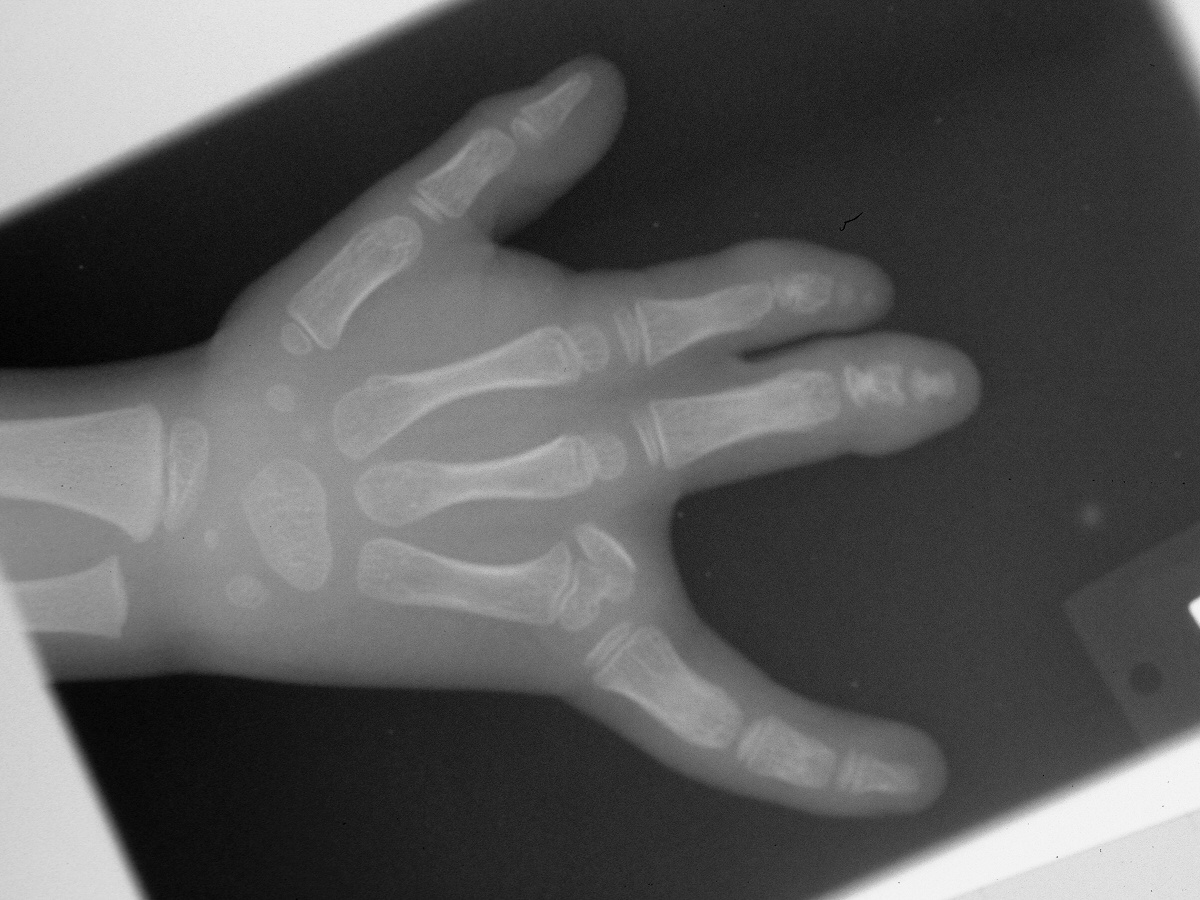

Further growth allowed better evaluation of the ulnar skeletal components.

The second procedure included web deepening with a three-flap plasty and closing wedge osteotomy to realign the small finger  metacarpophalangeal joint.

Postop Xray.